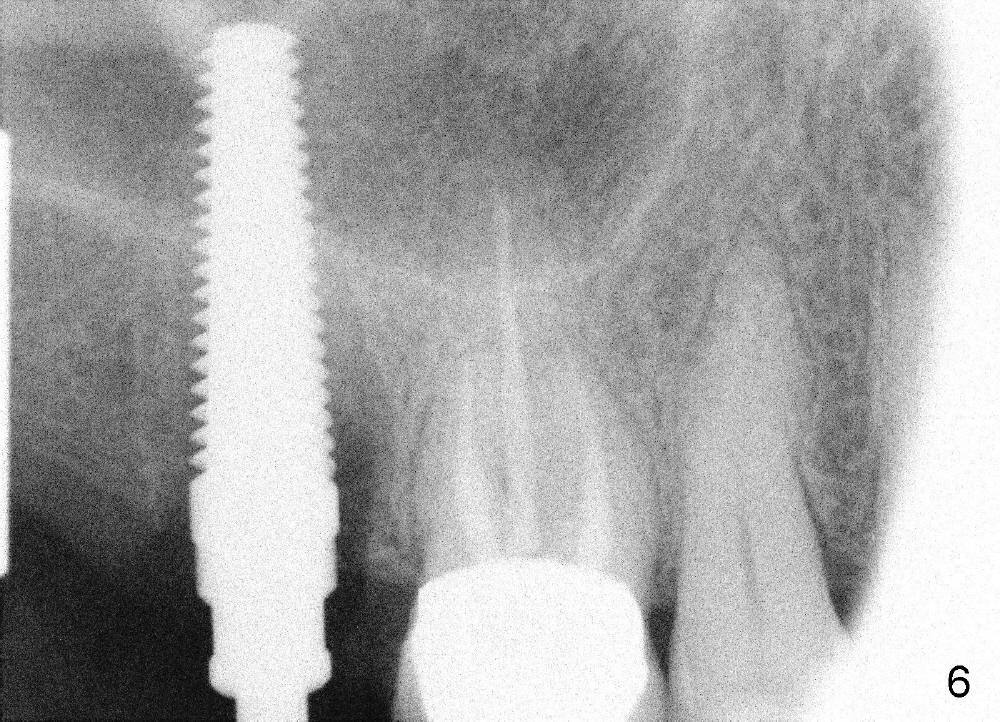

A 51-year-old lady has multiple restorations (Fig.1-3), e.g., amalgam (A in Fig.1) of the upper right 2nd molar as well as history of pulpotomy. The 1st molar has periapical radiolucency (* in Fig.1) and needs root canal therapy. The lower 3rd molar occludes (Fig.2 arrow) with the upper 2nd molar. The latter fractures subgingivally (Fig.3 <) and is extracted with a large MB root (Fig.4) and MB socket (Fig.5). The gingival one third of the palatal wall is defective, as indirectly indicated by granulation tissue palatally (Fig.5 <). So the osteotomy for the immediate implant will not be placed in the palatal socket. The septum is pointed coronally. The pointed portion of the septum is removed; initial osteotomy is formed by 1.5 mm pilot drill in the septum, followed by 2-5 mm osteotomes with the depth of 17 mm. The enlarging osteotomy is deviating buccally; drills are being used to move the osteoomy palatally without much success. When a 5 mm tap is inserted, it is stable and appears to be inside the maxillary sinus (Fig.6). In fact the osteotomy has bony walls around (Fig.7 <), including apical, when the tap is removed. Preop PA shows that the palatal root is apical to the sinus floor (Fig.1 between arrows).